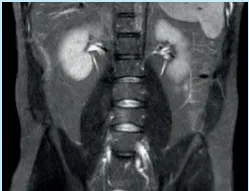

Every year, over 60 million magnetic resonance imaging (MRI) scans are performed worldwide. This technology has fundamentally changed the way modern medicine diagnoses diseases. As a non-invasive medical imaging technique, MRI can generate detailed three-dimensional images of the inside of the human body, helping doctors accurately diagnose various conditions. In Hong Kong, MRI examinations have become an important diagnostic tool. They are not only used to examine neurological diseases such as brain and spine conditions but also to diagnose a variety of diseases including joint, soft tissue injuries, and cancers.

Magnetic resonance imaging (MRI) utilizes the hydrogen atoms in the abundant water molecules within the human body for imaging. Since the human body is composed of about 70% water, this allows MRI to produce clear internal images. When the body is placed in a strong magnetic field, the hydrogen atoms align in a specific direction. By emitting radio waves at a specific frequency, these hydrogen atoms are excited and resonate. When they return to their original state, they release energy, a process known as nuclear magnetic resonance.

MRI can detect subtle changes within the body’s structures, which is beneficial for early diagnosis. Because magnetic resonance imaging does not involve radiation, it is suitable for examining any part of the body (such as bone and soft tissue structures). The main uses of MRI include examinations of the brain, spinal cord, ligaments, joints, muscles, heart, blood vessels, breasts, abdomen, and pelvis. It holds significant value for cancer diagnosis, tumor monitoring, fatty liver assessment, and cartilage repair.